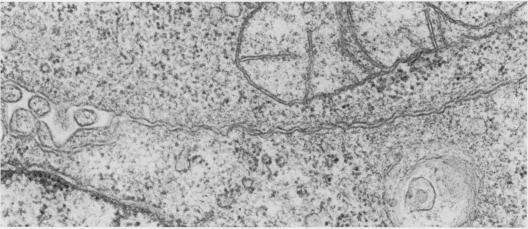

Rat ascites hepatoma AH109A cells (present as a free form in vivo) can aggregate and then develop well-defined tripartite junctional complexes, including intermediate junctions, desmosomes and focal tight junctions, on incubation with a glycoprotein separated from rat ascites hepatoma AH136B cells (forming cell islnds in vivo). The development of binding structures was strongly inhibited by actinomycin D. AH109A cells or rat ascites hepatoma YS cells (present as a free form in vivo) previously treated with the glycoprotein for 24 h, when inoculated i.p., proliferated as free cells in the ascitic fluid, like the untreated cells. AH109A cells actively proliferating in the skin do not form any junctional complexes. The reason for the failure of island formation by AH109A cells or YS cells in vivo is discussed.

大鼠腹水肝癌AH109A细胞(在体内以游离形式存在)在与从大鼠腹水肝癌AH136B细胞(在体内形成细胞岛)分离的一种糖蛋白一起孵育时,能够聚集,然后形成明确的三联连接复合体,包括中间连接、桥粒和紧密连接。结合结构的形成受到放线菌素D的强烈抑制。预先用该糖蛋白处理24小时的AH109A细胞或大鼠腹水肝癌YS细胞(在体内以游离形式存在),腹腔注射接种后,会像未处理的细胞一样在腹水中以游离细胞的形式增殖。在皮肤中活跃增殖的AH109A细胞不形成任何连接复合体。文中讨论了AH109A细胞或YS细胞在体内未能形成细胞岛的原因。